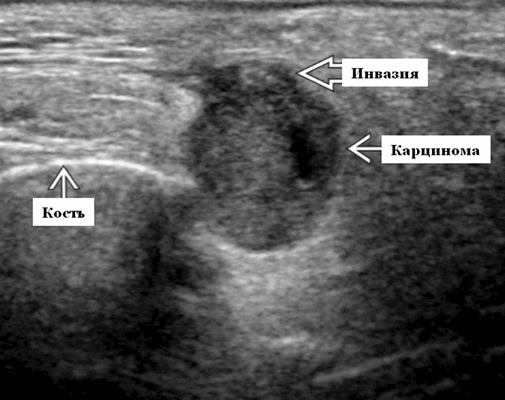

Серошкальное УЗИ. Одиночные или множественные гипоэхогенные образования в известном распределении внутрипаротидных лимфоузлов. Хорошо выраженный или слабо окаймленный (экстранодальное распространение). Экстранодальное распространение. Обратите внимание на местную инвазию интрапаротидной наружной сонной артерии (ВСА), ретромандибулярной вены или экстрапаротидных мягких тканей. Аномальная внутренняя архитектура ± эхогенные ворота. Однородный или неоднородный вид с внутренними кистозными участками в некротических узлах ± метастазы в шейные лимфатические узлы

Наиболее распространенным злокачественным новообразованием, происходящим в слюнных железах является мукоэпидермоидная карцинома и аденоидные кистозные карциномы. Плоскоклеточная карцинома, ацинарно-клеточная карцинома и аденокарциномы встречаются реже. Менее 30% фокальных очагов в околоушной железе, выявляемых на УЗИ, являются злокачественными, в то время как почти 50% очаговых образований в подчелюстной железе являются злокачественными. В отличие от доброкачественных новообразований, злокачественные опухоли могут быстро расти, могут быть мягкими или болезненна при пальпации, а также вызывают парез лицевого нерва или его паралич.

Мукоэпидермоидная карцинома возникает в основном у людей между 30 и 50 годами. Макроскопический вид опухоли, а также ее ультразвуковая визуализация, в основном, зависит от уровня злокачественности. Хорошо дифференцированные опухоли на УЗИ могут быть похожи на доброкачественные опухоли. Аденоидная кистозная карцинома, которая является медленно растущей опухолью, показывает определенную тенденцию к инфильтрации в нерв (а значит возникает боль), и часто дает поздние метастазы. Классические черты на УЗИ при малодифференцированных или больших злокачественных новообразованиях слюнных желез такие же, как в других органах или тканях.

К особенностям злокачественных новообразований слюнных желез при ультразвуковой диагностике относятся следующие: неправильная форма, неровные границы, размыты поля и неоднородная гипоэхогенная паренхима. Однако, злокачественные опухоли также могут быть однородными и хорошо определенными. Внутренняя структура злокачественной опухоли на УЗИ у нас может быть не только солидной, но и кистозной или кистозно-солидной. Злокачественные опухоли могут иметь округлую форму, похожую на плеоморфную аденому.